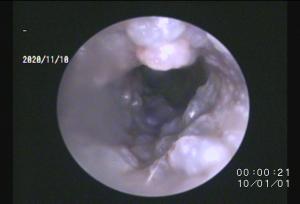

左耳

ドロッとした耳垢ですね・・。

両耳の細胞診をしてみると構成されている菌バランスや検出される菌の種類が異なります。

なので・・・

点耳薬の種類を右と左で使い分けしなければいけません(ちょっと面倒ですが・・)

このように、左右で匂いや耳垢の性状が異なる場合は注意が必要です。

当院では、細胞診を行い適切な抗菌薬の使用や消炎剤の選択をおこなっています。

地味に・・点耳薬の選択は症状改善の大事な要素になりますので治りにくい場合は再確認してみましょう!